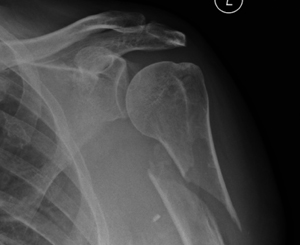

This very active 88 year-old lady sustained a displaced fracture of her humerus following a simple fall. Fixation with a locking-plate allowed early return to function.

52 year-old lady with a displaced fracture of the proximal humerus requiring surgical fixation with a long locking-plate.

This man sustained a locked posterior fracture dislocation of the shoulder. Open reduction and internal fixation with a locking plate.

This elderly patient sustained a bad fracture-dislocation of the shoulder. This was treated with a reverse shoulder replacement where the normal ball & socket joint gets converted to a socket & ball joint.

The fracture-dislocation of this patients shoulder was treated by open reduction and internal fixation using a Titanium locking-plate.